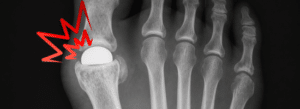

The Cartiva Synthetic Cartilage Implant (SCI) is a polyvinyl alcohol (PVA) hydrogel device designed to treat big toe arthritis (hallux rigidus) by preserving joint motion and avoiding fusion surgery.

The most common failure mechanism is subsidence, where the implant sinks into surrounding bone.

The Cartiva implant is a synthetic cartilage device made from polyvinyl alcohol hydrogel, designed to treat arthritis in the big toe while preserving joint motion.